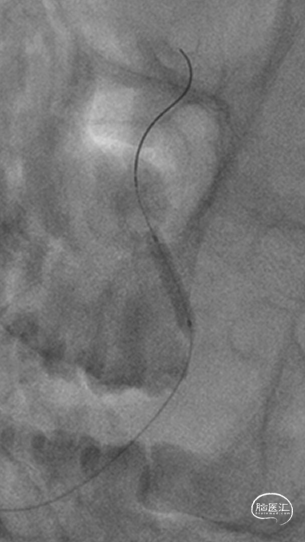

气管插管全麻。6F 指引导管、5F多功能管、泥鳅导丝同轴,将指引管放置于右侧椎动脉V2段。路径图下,将Synchro-14 微导丝引导SL-10微导管导管小心通过椎基底动脉次全闭塞处,放至右侧大脑后动脉P1段。更换为Trensend-300cm微导丝,撤出SL-10微导管。